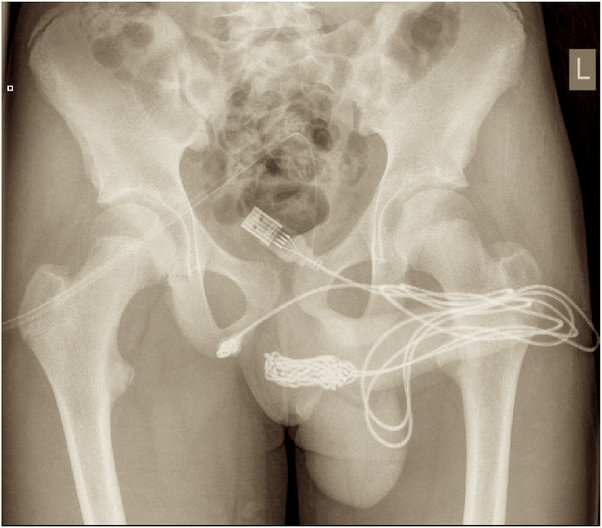

An X-ray was ordered immediately. What it revealed was far stranger than anyone expected.

The X-Ray That Revealed the Unthinkable

The images showed a long, coiled object filling the patient’s bladder—with one end dangling out of his urethra. It wasn’t just a small foreign body. It was a 6-meter (20-foot) plastic cable, tightly packed inside him.

An immediate X-ray revealed a chilling sight: a 6-meter (20-foot) plastic cable coiled inside his bladder, with one end dangling through his urethra. The discovery triggered a race against time—the cable had caused a complete urinary blockage, risking kidney failure, sepsis, or bladder rupture.